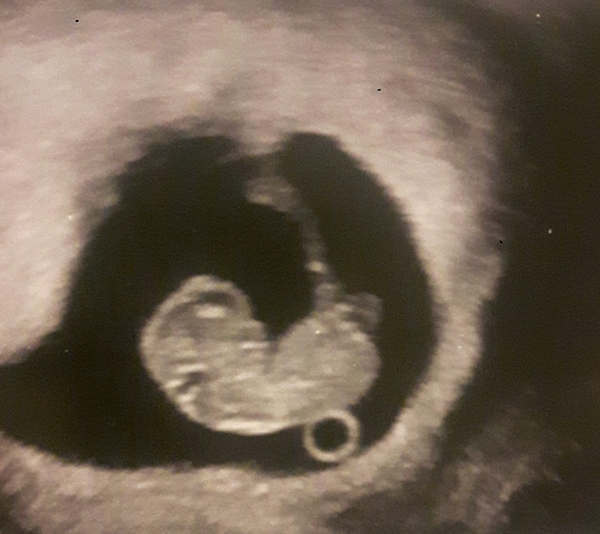

Hi ive been terrified to join after have a mmc early last year but have had a scan today at 9 weeks and everything looks great so feeling abit more positive. Sorry to hear about everyone's losses it is a devastating thing to have to go through.x

sugar that's a lovely scan pic

Wow! What an incredible scan photo! Congratulations sugar

Welcone sugar! Lovely scan pic.

That's a very clear scan pic, how lovely.